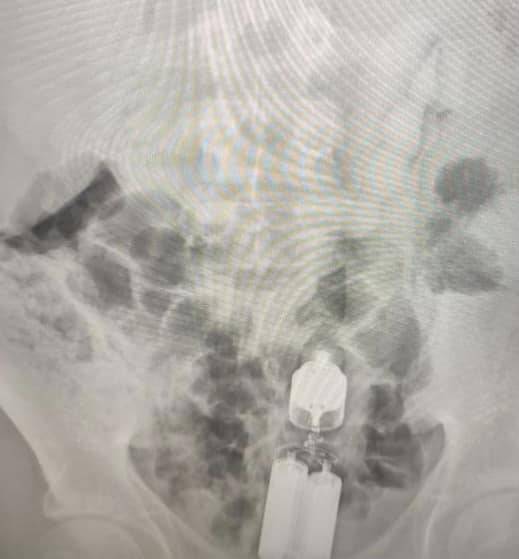

Один із останніх таких випадків стався з 16-річним хлопцем, у животі якого лікарі виявили вібратор. Три години вібратор продовжував працювати всередині пацієнта, приводячи до дискомфорту, болю в животі та кровотечі.